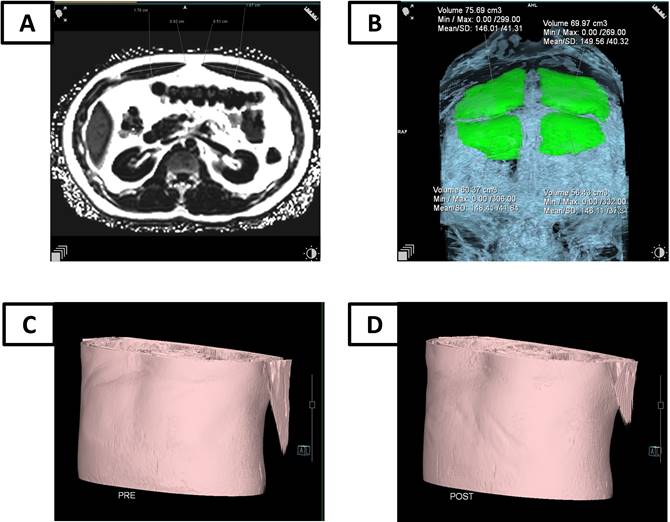

MRI examination

Figure 2

The MRI examination for RAM. (A) The thickness evaluation by MRI; (B) The volume evaluation by MRI; (C) MRI simulation of abdominal morphology before HIFEM training; (D) MRI simulation of abdominal morphology three months after HIFEM training.